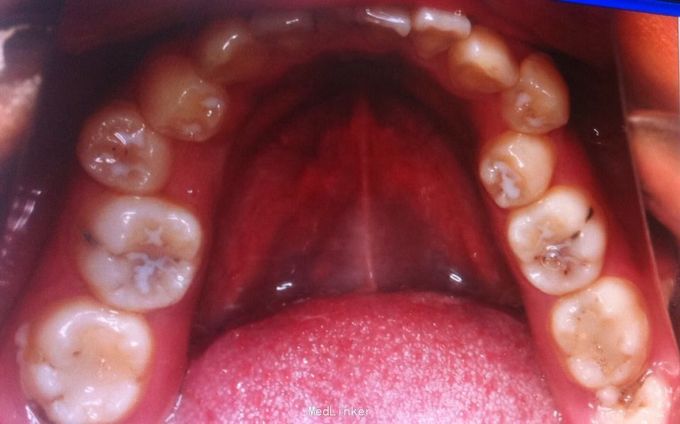

恒牙期 左侧磨牙中性关系,右侧远中关系 前牙三度深覆合 上合牙列中度拥挤,下颌重度拥挤 下颌中线偏右 关节有弹响

安氏二类,牙列拥挤 拔牙矫治,拔除14、24、34、44,强支抗,排齐整平上下牙列,矫治后磨牙中性关系,前牙覆合覆盖正常,面型略改善